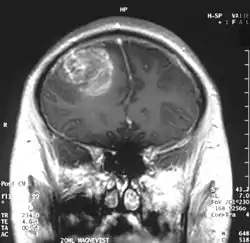

- اختبارات التصوير: وغالبًا ما يستخدم التصوير بالرنين المغناطيسي للمساعدة في تشخيص أورام الدماغ. في بعض الحالات، قد يتم حقن صبغة (مواد تباين) خلال وريد في ذراع المريض أثناء دراسة التصوير بالرنين المغناطيسي للمساعدة في إظهار الاختلافات في أنسجة الدماغ.

قد يساعد عدد من مكونات التصوير بالرنين المغناطيسي المتخصصة — بما في ذلك التصوير بالرنين المغناطيسي الوظيفي، وتصوير التروية بالرنين المغناطيسي وتنظير الطيف بالرنين المغناطيسي — في تقييم الطبيب للورم وخطة العلاج.